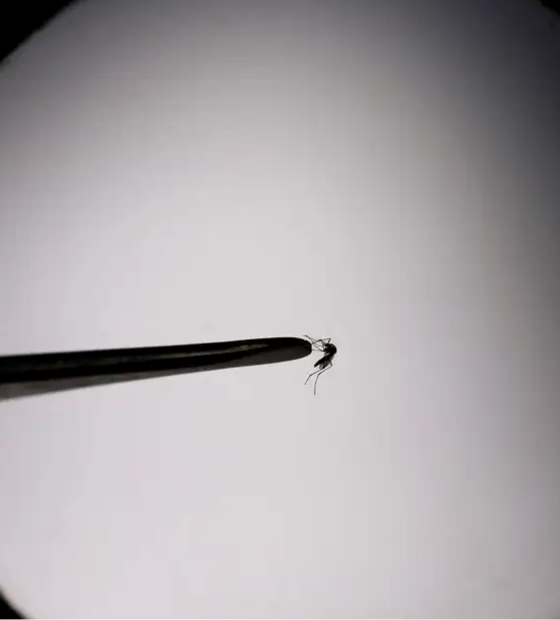

Brasil se aproxima de 6 milhões de casos e 4 mil mortes por dengue

Números são divulgados pelo Ministério da Saúde